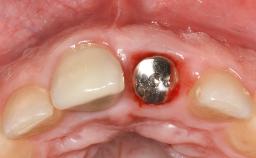

Peri-Implantitis Modified by the Presence of Submucosal Excess Cement: Reconstructive Therapy and a Ten-Year Follow-up

This case outlines the reconstructive therapy by Giovanni Salvi resulting in defect fill and inflammation-free peri-implant soft tissues at 10-year follow up. This case highlights the importance of regular monitoring of implants during supportive therapy.